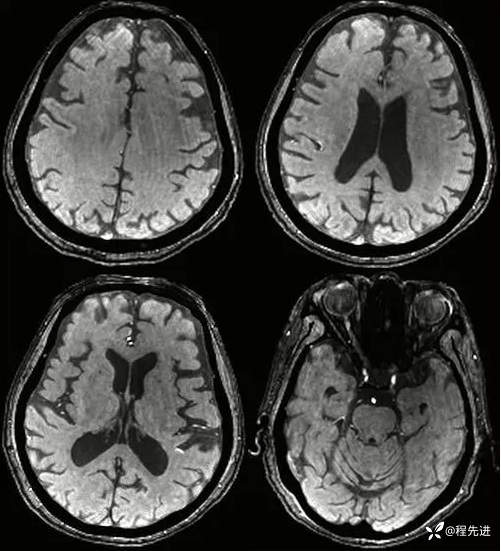

QSM:

SWI: